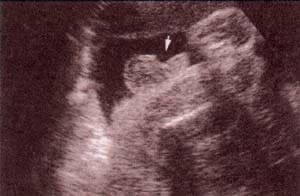

Diagnóstico Prenatal -  genitales externos xx Diagnóstico Prenatal -  genitales externos xx

fig. 49.– (a). genitales externos xx. labios mayores (1) . 32 semanas. fig. 49. – (b). labios menores fusionados (2). 32 semanas.